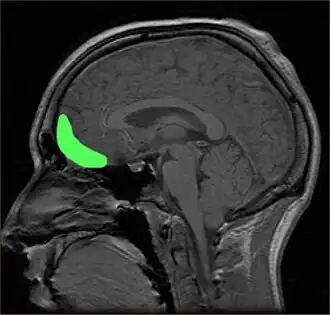

Op deze MR-scan is de cortex orbitofrontalis aangegeven in groen.

De cortex orbitofrontalis[2] of orbitofrontale cortex[1] is het onderdeel van de prefrontale schors van de grote hersenen.[2]. Het schorsgebied ligt boven de oogkassen (Latijn: orbitae). Voor het meer centrale deel wordt ook wel de benaming ventromediale prefrontale cortex gebruikt.